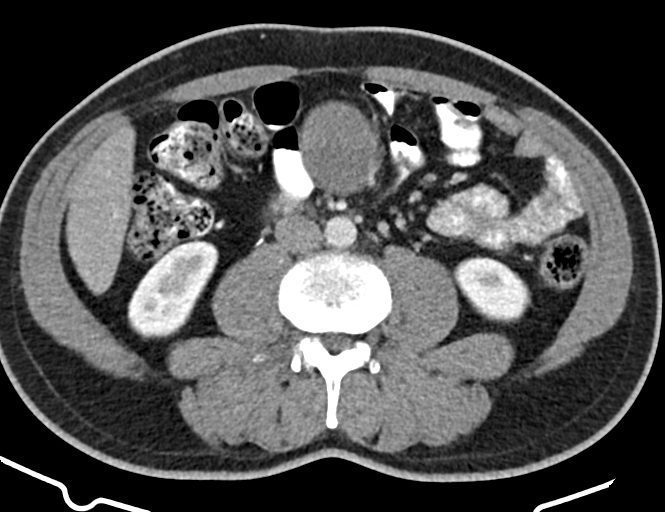

ام آر آی آتروفی عضلانی کتف بیمار

ام ار آی کتف یک روش تصویربرداری است که به وسیله آهنرباهای قدرتمند از قسمت کتف تصاویری ایجاد می کند. این نوع تصویربرداری از تشعشعات استفاده نمی کند. در این کیس آتروفی عضلانی کتف به همراه پارگی تاندون بالاخاری، بورسیت ساب دلتوئید و افیوژن مفصل دیده می شود.

گزارش پزشک :

LEFT SHOULDER MRI

(Without contrast)

Technique: Axial T1 and GE , coronal T1 , T2 , sagittal T1 , T2 .

REPORT:

The humeral head has normal configuration and articulates properly and parallelism with the normally developed glenoid .

The articular surfaces are smooth and show normal cortical thickness .

The bone marrow displays homogeneous , fat – equivalent signal intensity .

The glenoid labrum is intact on all sides .

The biceps tendon appears normal and occupies a normal position in the bicipital groove.

The other muscles that cover the shoulder joint appear normal , as do imaged portions of the lungs and soft tissues .

– Complete tearing of supraspinatus tendon with grade 2 retraction and muscle atrophy

– AC joint hypertrophy with subacromial – subdeltoid bursitis

– Glenohumeral joint effusion

are seen.